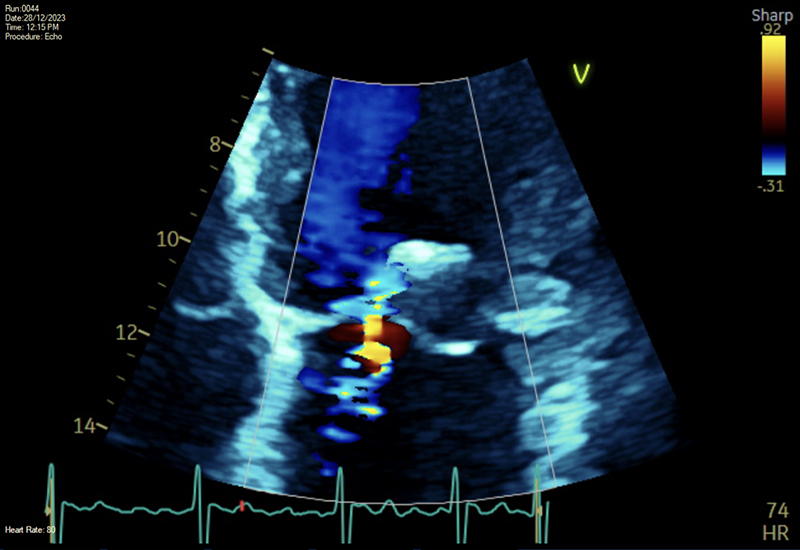

A previously fit and healthy 60-year-old man presented with recurrent and severe pulmonary oedema. Clinical assessment and an initial transthoracic echocardiogram (TTE) showed a flail posterior mitral valve (MV) leaflet (P2) associated with chordal rupture and torrential eccentric MR (figure 1). Left ventricular (LV) function, in this off-loaded state, was preserved with an ejection fraction (EF) of 60%.

To break this impasse, an uncomplicated transcatheter edge-to-edge mitral valve repair (TEER) was undertaken under general anaesthesia using Pascal with a reduction of the left atrial (LA) V-wave from 50 mmHg to only 17 mmHg following double-clip deployment (figure 2). A post-procedural TTE demonstrated Pascals in situ with only mild-to-moderate residual MR, a mean transmitral gradient of only 3 mmHg, and just modest LV impairment with an EF of 49%. The patient was subsequently switched to oral diuretics and remained haemodynamically stable.